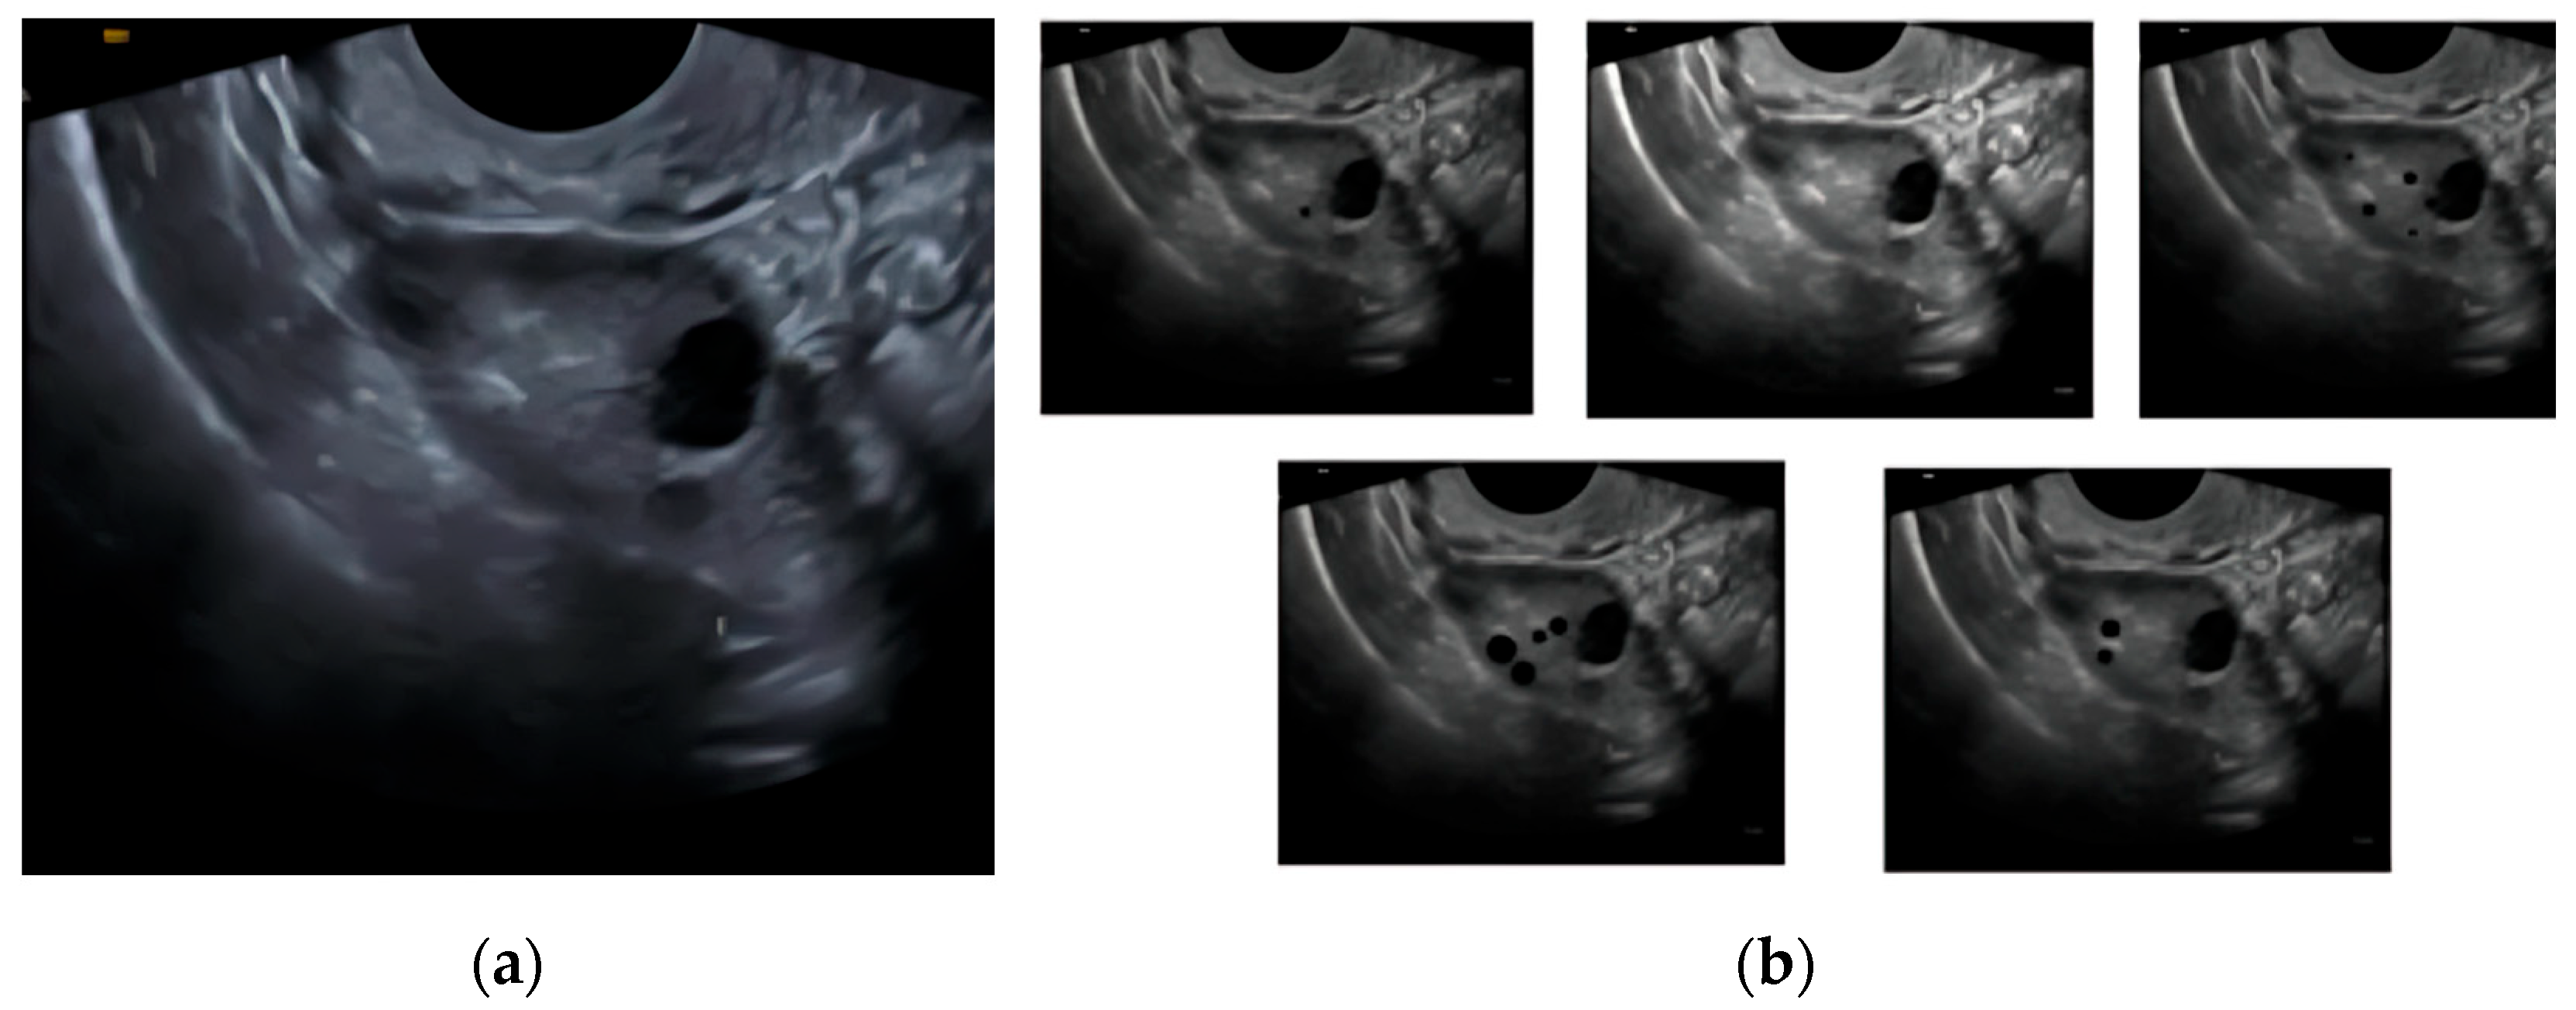

The CNN model uses ultrasound transvaginal scans for around 250 synthetically generated cases under 5 classes divided on the basis of ovarian function (Figure 1). The classes are active, inactive, declining, perimenopausal, and anomalous [9]. There are around 50 cases for each case in order to simulate realistic transvaginal ultrasound scans and make sure that the model learns most visual features of the various ovarian functionality classes.

Figure 1. Demonstration of synthetic dataset creation: (a) base transvaginal image used for synthesis; (b) derived class images (active, inactive, declining, perimenopausal, and anomalous).